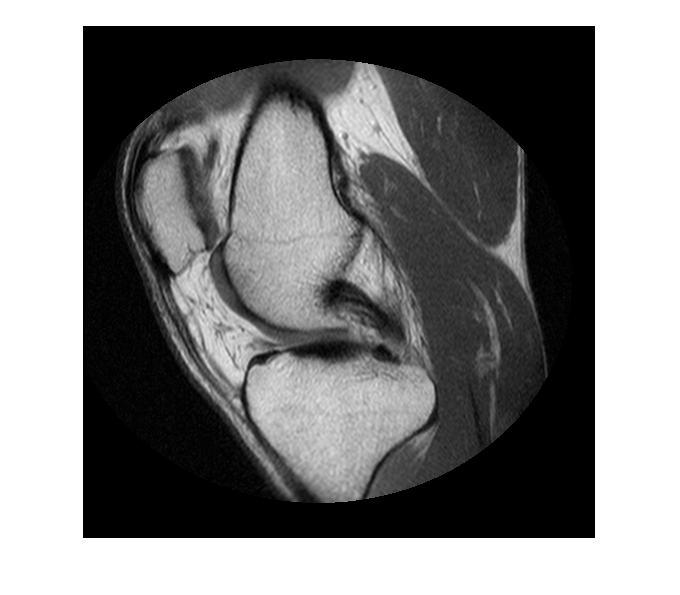

MRI データをワークスペースに読み取ります。

im = dicomread('knee1.dcm');

イメージを表示します。

figure hImage = imshow(im,[]);